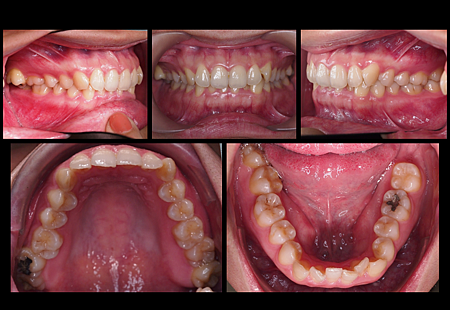

先說明一下我的牙齒狀況

外觀正常沒爆牙,剩3顆智齒

上排牙齒成ㄇ字型,門牙內傾

上排右側臼齒外露沒有跟下排對咬,

下排擁擠錯咬,有嚴重深咬